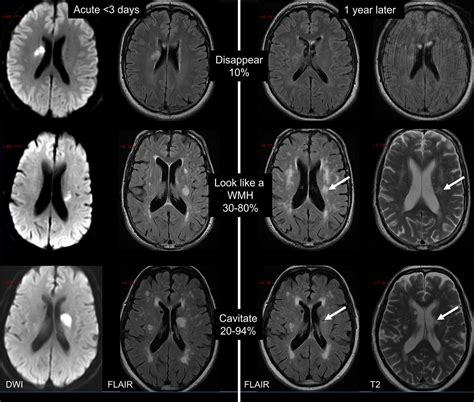

• Imaging Studies: Such as ultrasound, MRI, or CT scans to visualize the blood vessels and assess their condition.